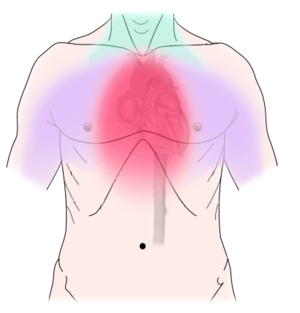

Non-dental causes of toothache are much less common as compared with dental causes. In a toothache of neurovascular origin, pain is reported in the teeth in conjunction with a migraine. Local and distant structures (such as ear, brain, carotid artery, or heart) can also refer pain to the teeth.[34]:80,81 Other non-dental causes of toothache include myofascial pain (muscle pain) and angina pectoris (which classically refers pain to the lower jaw). Very rarely, toothache can be psychogenic in origin.[9]:57–58

Establishing a diagnosis of nondental toothache is initially done by careful questioning about the site, nature, aggravating and relieving factors, and referral of the pain, then ruling out any dental causes. There are no specific treatments for nondental pain (each treatment is directed at the cause of the pain, rather than the toothache itself), but a dentist can assist in offering potential sources of the pain and direct the patient to appropriate care. The most critical nondental source is the radiation of angina pectoris into the lower teeth and the potential need for urgent cardiac care.[9]:68

Non-dental sources of pain often cause multiple teeth to hurt and have an epicenter that is either above or below the jaws. For instance, cardiac pain (which can make the bottom teeth hurt) usually radiates up from the chest and neck, and sinusitis (which can make the back top teeth hurt) is worsened by bending over.[9]:56,61 As all of these conditions may mimic toothache, it is possible that dental treatment, such as fillings, root canal treatment, or tooth extraction may be carried out unnecessarily by dentists in an attempt to relieve the individual's pain, and as a result the correct diagnosis is delayed. A hallmark is that there is no obvious dental cause, and signs and symptoms elsewhere in the body may be present. As migraines are typically present for many years, the diagnosis is easier to make. Often the character of the pain is the differentiator between dental and non-dental pain.